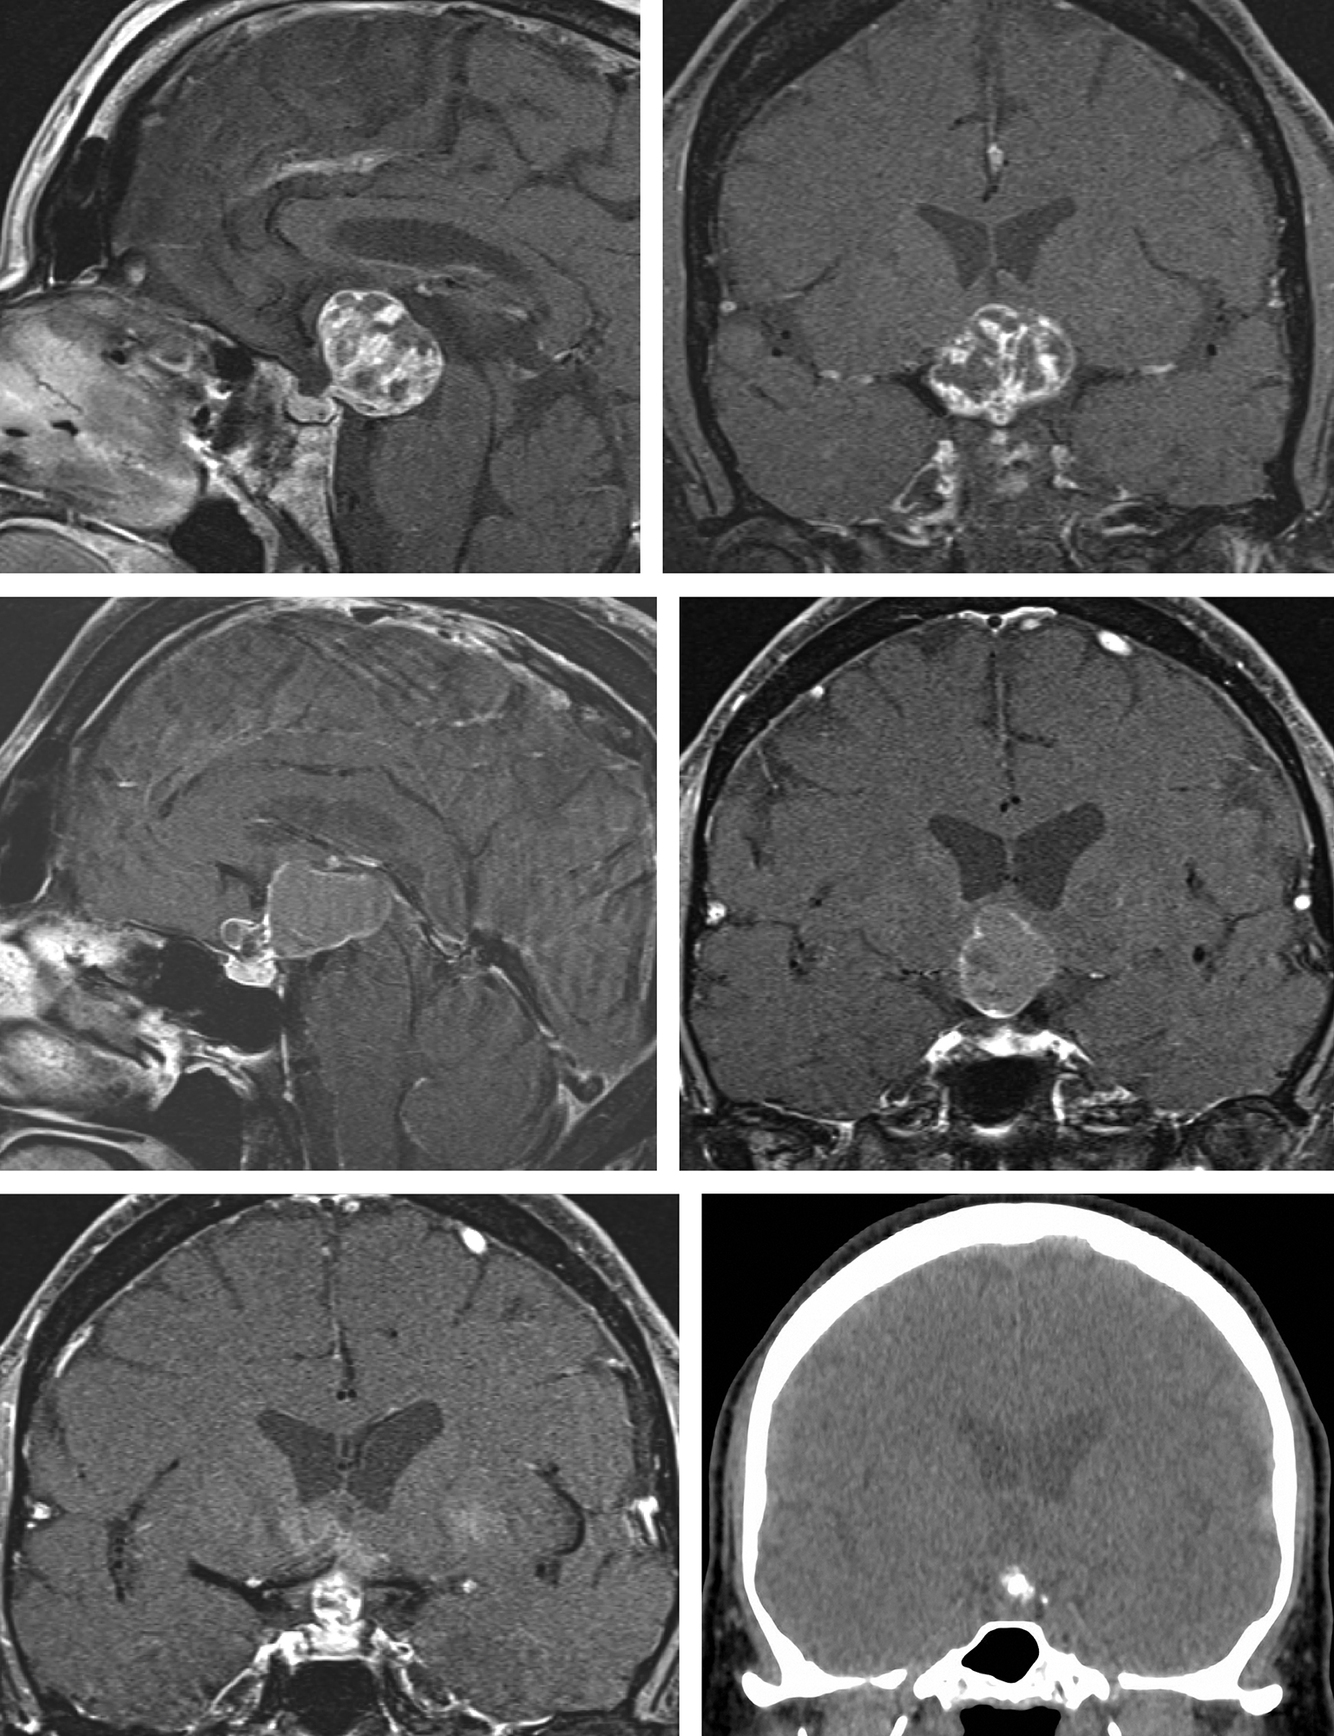

A meningioma often has a ___, which can be seen on imaging

A meningioma often has a dural tail, which can be seen on imaging

“CSF cleft”

Thin ribbon of CSF that can be seen around a meningioma, indicating that it is NOT attached to the brain parenchyma